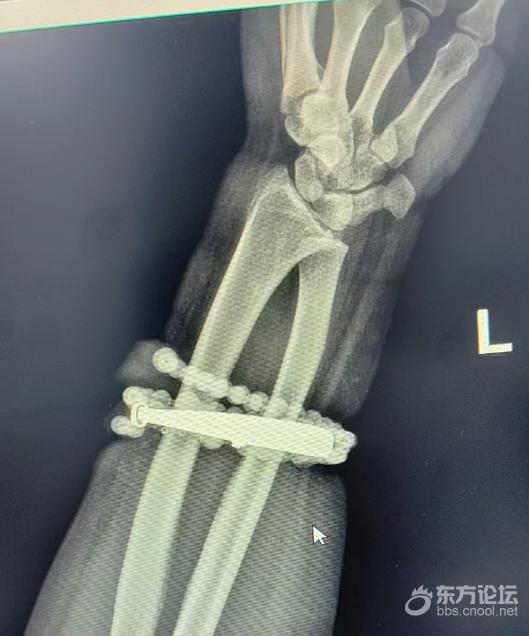

戴了十年没摘的手镯、串珠竟长进了肉里,还发炎了!近日,福建省宁德市闽东医院创伤骨科、手显微外科就接诊了这样一位患者。 ![]() 33岁的龚女士(化名)手腕上的银手镯和串珠戴了近十年,几乎从未摘下来过。随着时间推移,龚女士的体重也有所增加,手腕逐渐被勒得紧绷,但她并未在意。 直到近半年,龚女士手腕的皮肤出现反复瘙痒、发红,以为是普通皮炎,便自行买药膏涂抹。 然而,就在两周前,龚女士的情况急转直下:手腕不仅疼痛加剧,还出现了明显的红肿,甚至有脓液渗出。她这才惊觉——手镯和串珠,已经有一部分“长”进了肉里,根本取不下来了! “这是典型的首饰长期压迫、摩擦,加上细菌感染,引发的慢性炎症和肉芽组织增生。”医生介绍,此时,手镯和串珠已经成了一个不断刺激皮肤、污染伤口的“病灶”,如果不尽快手术取出,感染可能进一步扩散,甚至危及生命或影响手臂功能。 ![]() 经过一个多小时的手术,医生们将手镯和串珠从厚厚的增生组织中完整剥离出来。目前,龚女士恢复良好,已顺利出院。 ![]() 医生提示 佩戴首饰要注意以下几点: 定期检查与清洁:戴首饰(尤其是戒指、手镯)应定期摘下,清洁首饰及佩戴部位的皮肤,保持干燥。 注意“贴合度”:随着体重增加、妊娠水肿等生理状况的改变,应及时调整或取下过紧的首饰,避免压迫局部血液循环。 警惕皮肤信号:佩戴部位一旦出现瘙痒、红肿、疼痛、破溃等不适症状,应立即摘下首饰,观察皮肤情况。若症状持续不缓解,切勿自行用药或“硬扛”,应立即到正规医院就诊。 碰到特殊情况应及时取下:在进行体力劳动、运动或接触化学品时,最好取下首饰,避免摩擦、损伤或化学腐蚀。 |